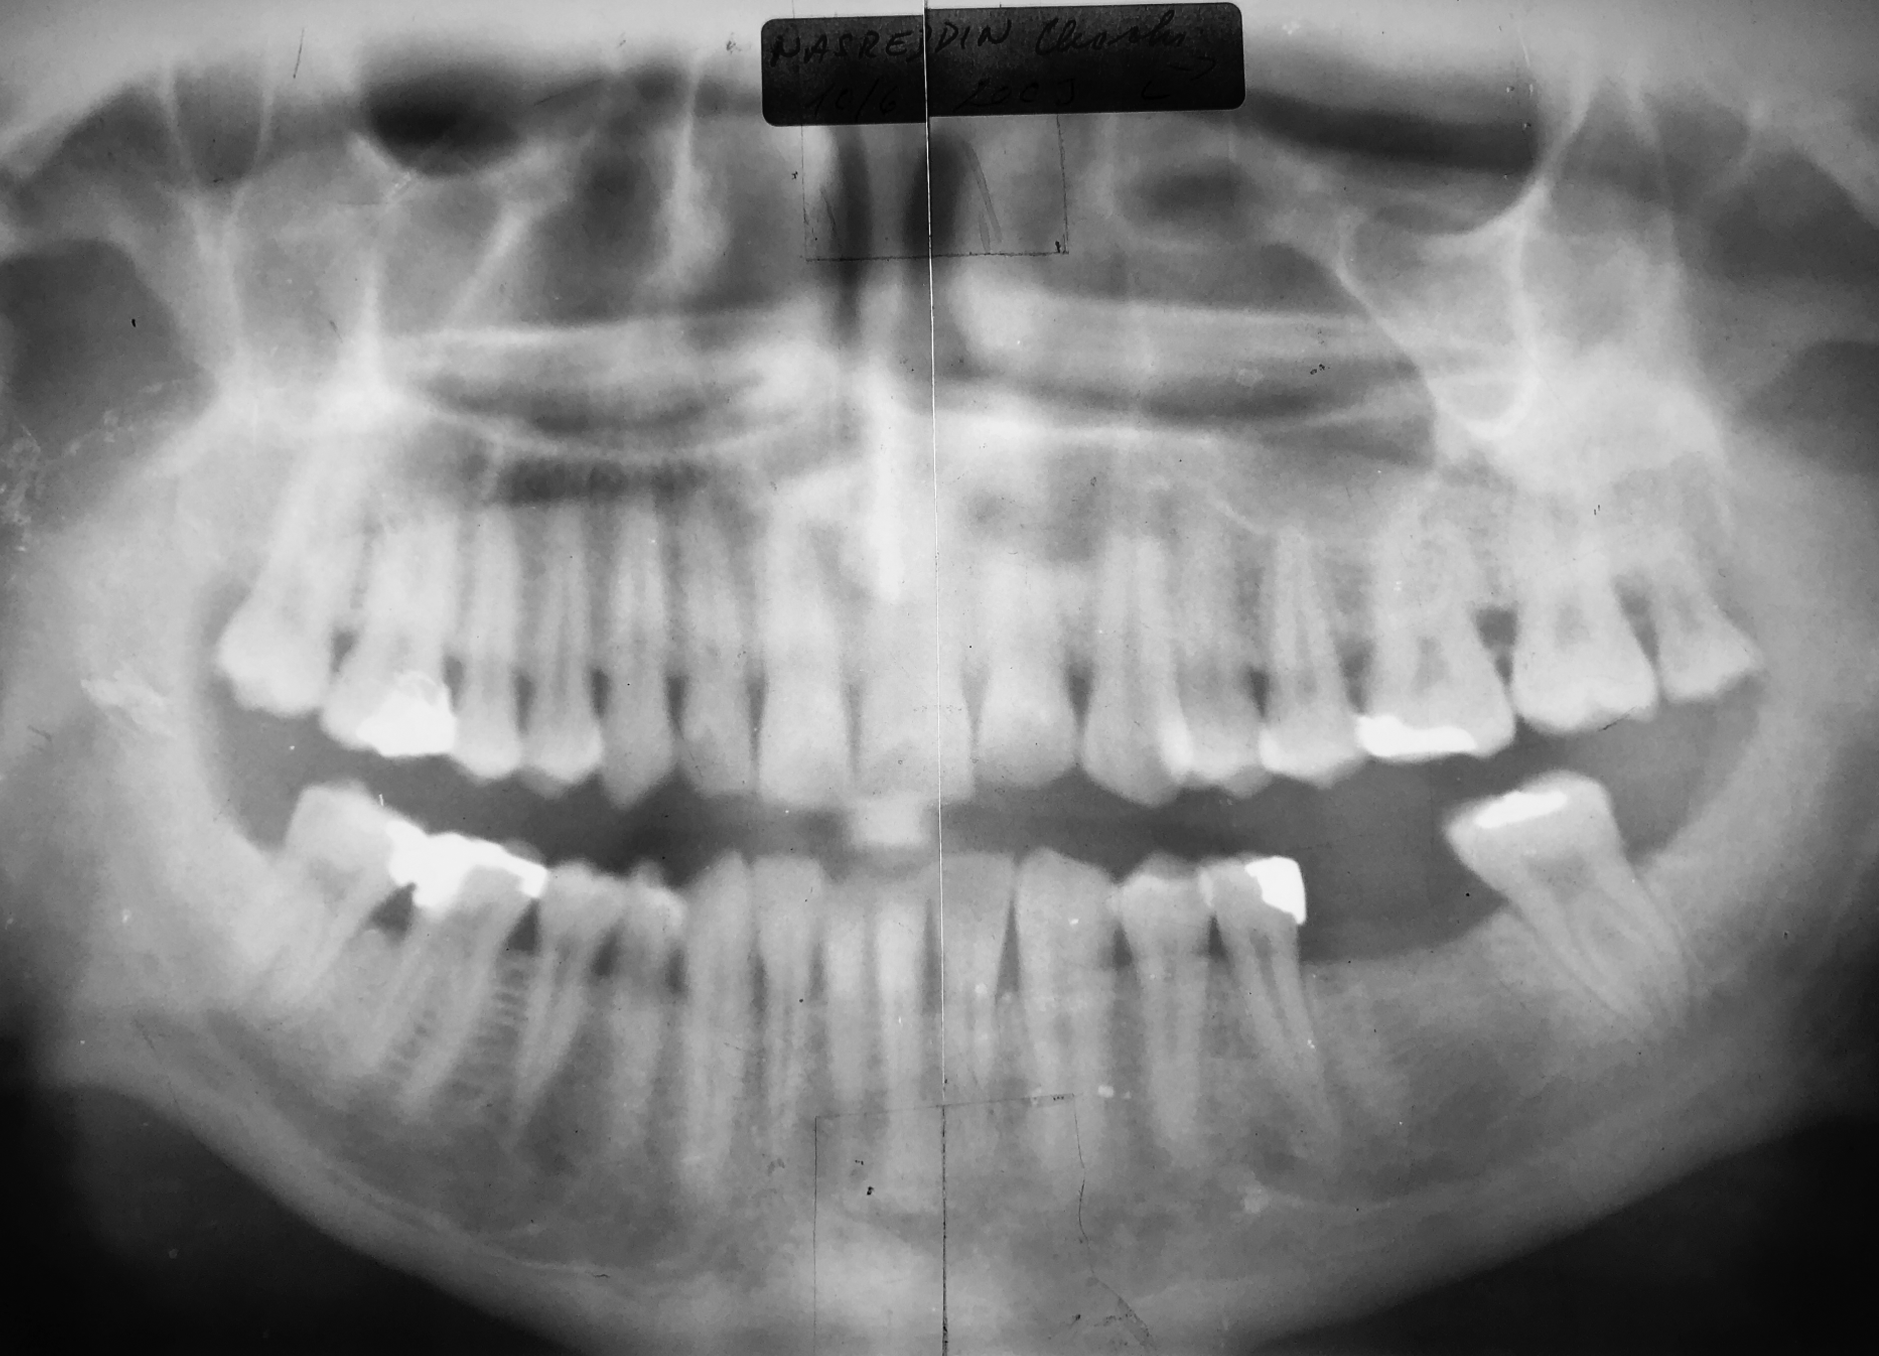

Initial situation of tooth 36 in May 2002. The tooth was subsequently extracted and the site was adequately prepared.